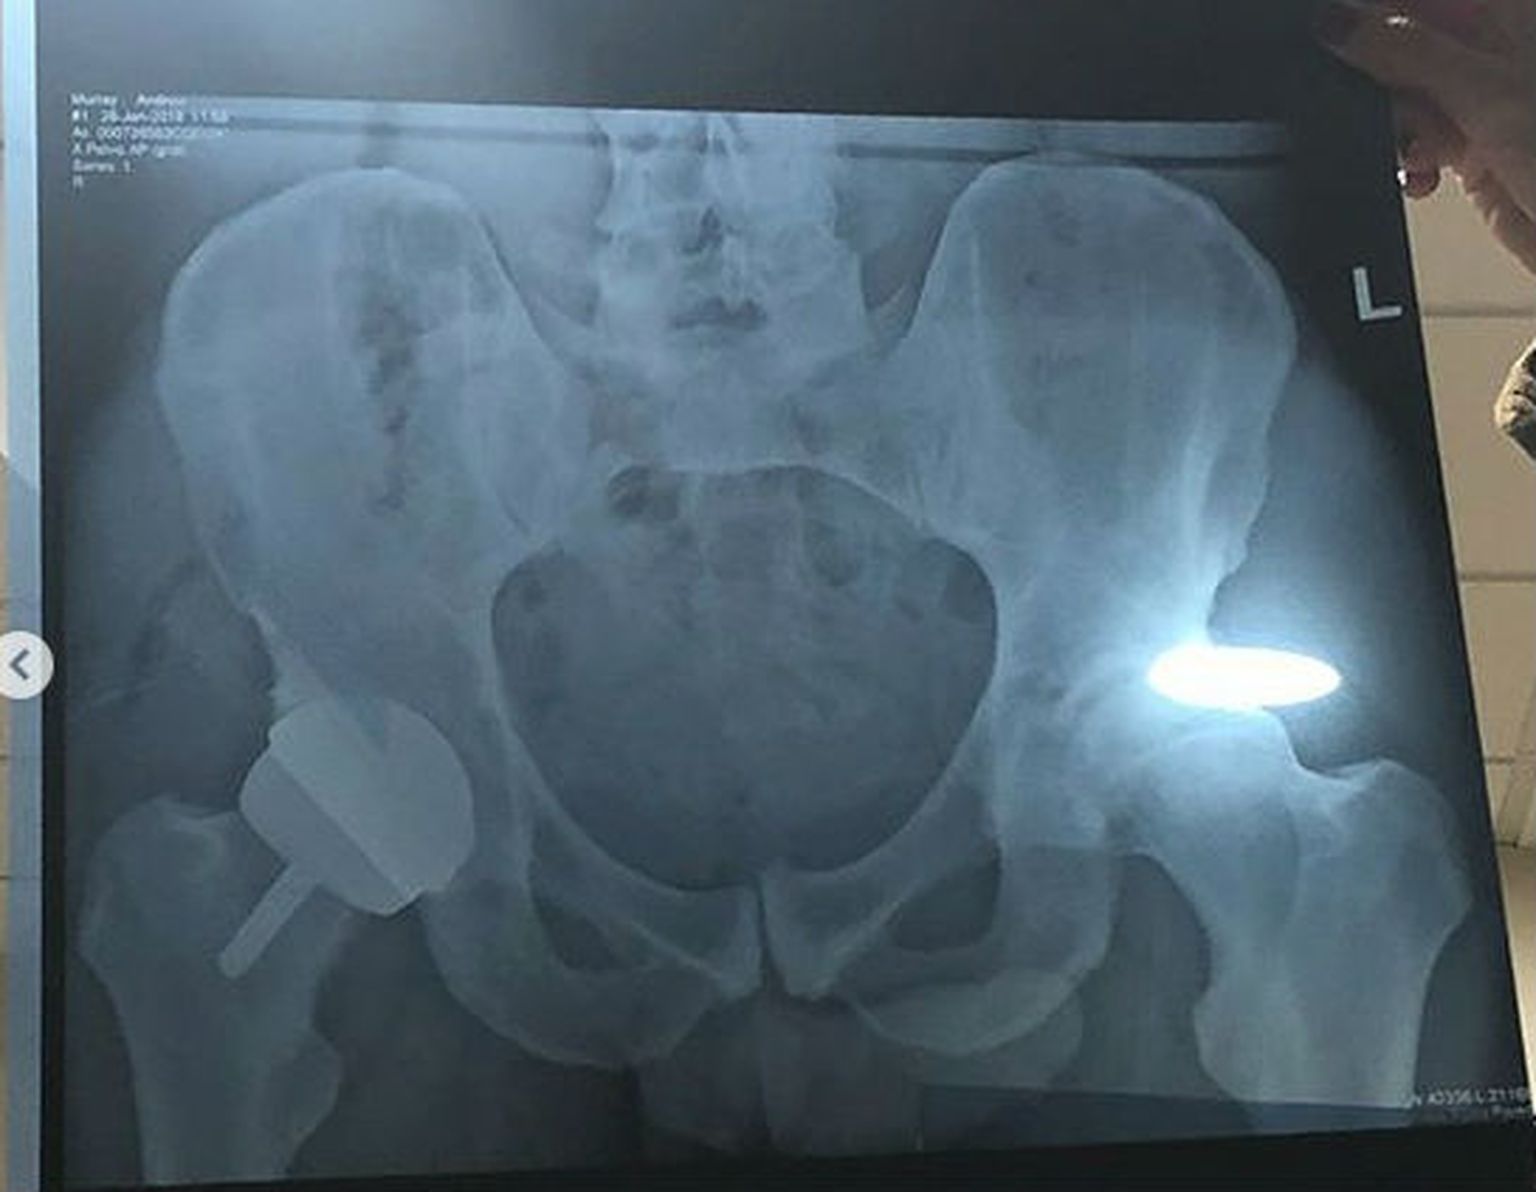

Umjetni kuk Andyja Murrayja (Instagram Andy Murray)

Andy Murray u suzama šokirao sve: ''Ne osjećam se dobro, dugo se borim, ne mogu više igrati''